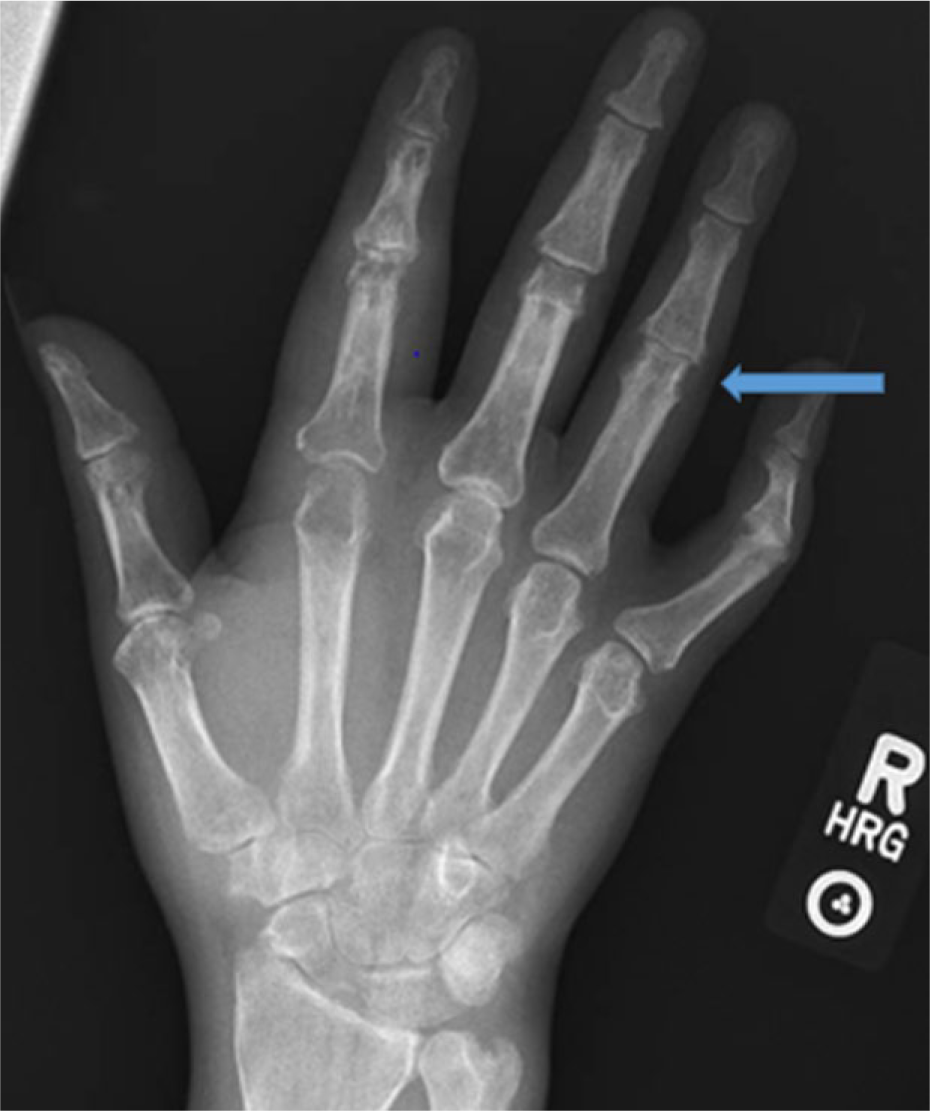

Hand X-ray showing erosions.

Hand X-ray suggesting early pencil cup deformity.

Musculoskeletal association with HS has been reported. Most note an association with skin flares and that it tends to occur years after the onset of skin disease. Most reports are anecdotal. We identified one multicenter analysis. 18 The prevalence of spondyloarthopathy in HS patients was found to be 3.7% in this study. Arthritis was usually seronegative, insidious in onset, occurring 2 to 15 years after the appearance of skin lesions. It usually starts as an oligoarthritis, but may progress to asymmetric polyarthritis. Spondyloarthritis/sacroiliitis is the most common joint manifestation noted. 19 Joints affected includes knees followed by elbow, wrist, ankle, and shoulder. Radiographic findings include soft tissue swelling, periarticular osteoporosis, joint space narrowing, erosions, and periosteal new bone formation. 20 The arthritis can persist after a flare. Laboratory evaluation in these cases may reveal mild anemia, leukocytosis, and elevated erythrocyte sediment rate. ANA positivity has been reported. HLA-B27 is usually negative. HS with arthritis is also reported in association with pyoderma gangrenosum, recurrent urethritis, conjunctivitis, and xerophthalmia. 19 An entity called PAPASH syndrome pyogenic (inflammatory) arthritis, pyoderma gangrenosum, acne, hidradenitis suppurativa has been discussed in the literature. 21